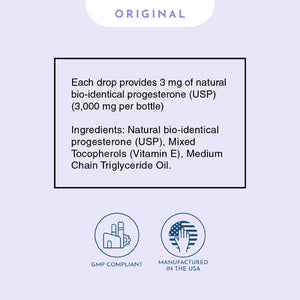

Our bio-identical progesterone is designed and formulated like no other. Unlike progesterone creams that are typically low concentration or contain thyroid suppressive oils, or progesterone pills / tablets that are largely inactivated by your liver, or suppositories that are prone to crystallization and can’t be absorbed… Progesterone Oil solves all of these problems. It’s highly concentrated at more than 10% progesterone, doesn’t crystalize, and contains a special solution allowing for close to 100% absorption. The secret lies in the special formulation with Vitamin E, which acts as a carrier to deliver the progesterone directly into the bloodstream. This makes it the quickest and most absorbable bio-identical progesterone source available.

Our Progesterone Oil contains 1 fl. oz. / 30 ml (over 3,000 mg per bottle) of pure, bio-identical progesterone, with high-quality Vitamin E, and pure non-GMO MCT oil (Coconut oil).